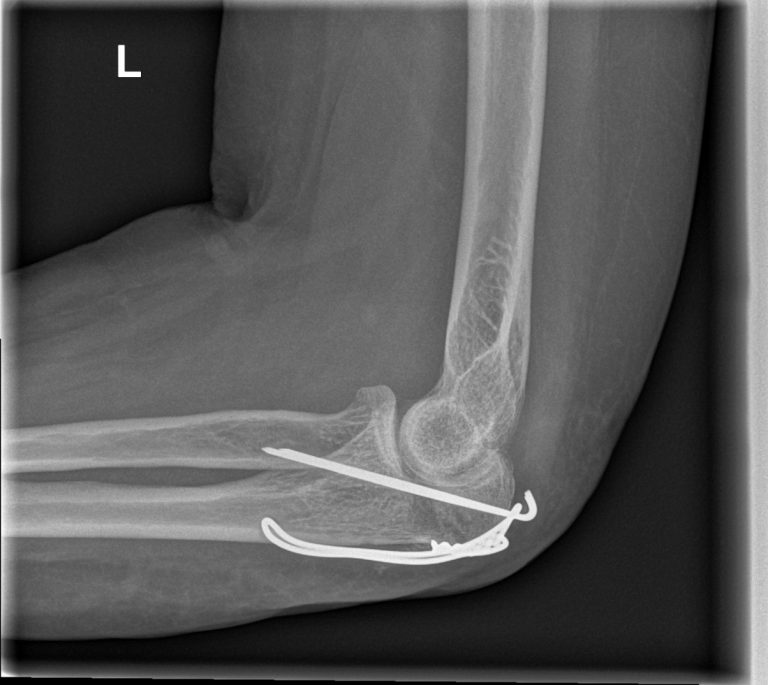

Olecranonfractuur

Breuk van de elleboogpunt na val of trauma? Olecranonfractuur diagnose en operatieve behandeling door ellebooogspecialisten in Orthopedie Turnhout.